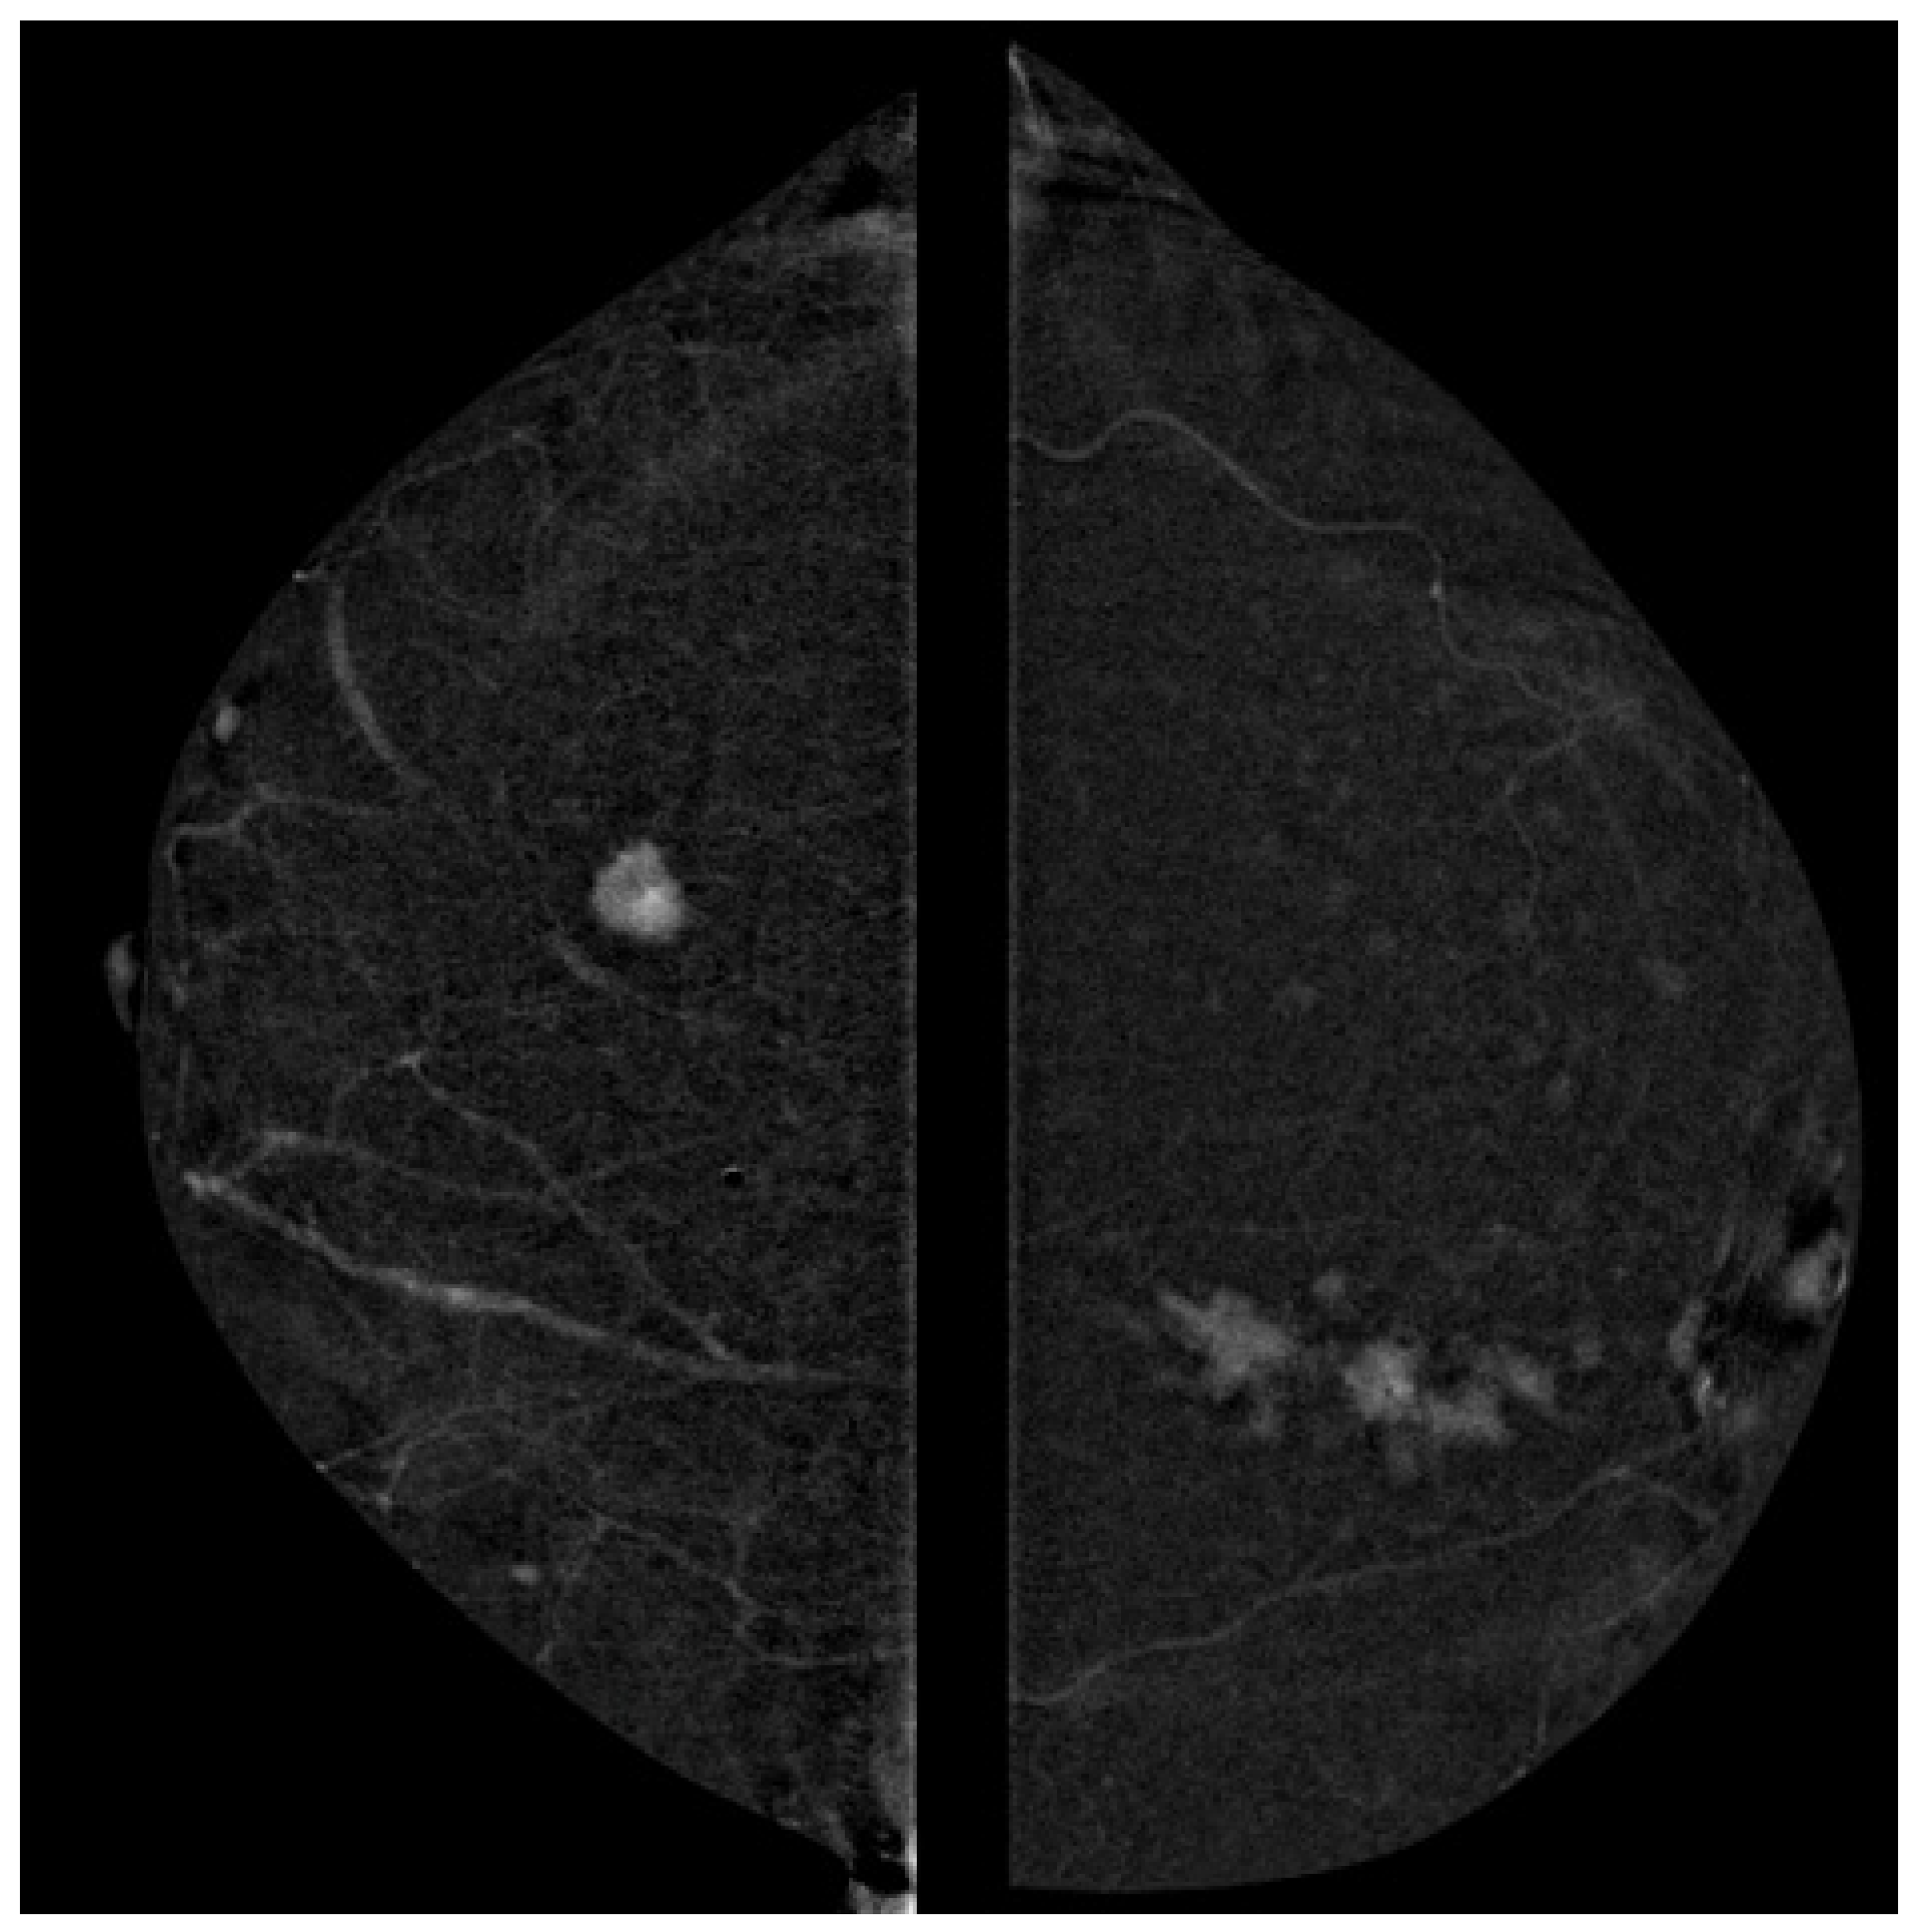

3.3. Correlation of Ki-67 and Enhancement Intensity

3.4. Correlation of Contrast Homogeneity and Tumor Grade